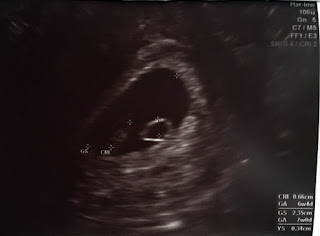

Ciąża - Pęcherzyk ciążowy z zarodkiem po transferze in vitro

Pęcherzyk ciążowy z widocznym zarodkiem:)